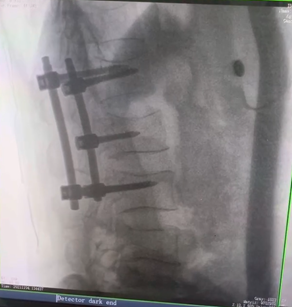

例如治療先天性脊柱側(cè)后凸畸形,由于脊柱自身復(fù)雜的解剖結(jié)構(gòu)限制,使得脊柱外科手術(shù)對(duì)于準(zhǔn)確度有著較高要求。以往我們只能采用傳統(tǒng)的正側(cè)位圖像來判斷螺釘置入的位置,現(xiàn)在三維C形臂特有的類CT斷層成像,使得治療過程可視化,立體化,在術(shù)中非常直觀地判斷螺釘植入的準(zhǔn)確度。可有效引導(dǎo)術(shù)者植入后路螺釘并切除半錐體。同時(shí)可以在術(shù)中實(shí)時(shí)驗(yàn)證手術(shù)效果。有效地縮短了手術(shù)時(shí)間,降低手術(shù)風(fēng)險(xiǎn),避免了不必要的術(shù)后翻修手術(shù)。